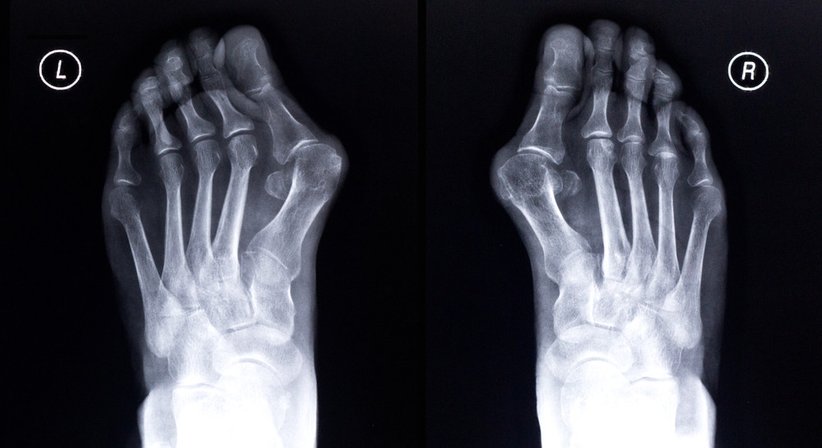

Beim Hallux valgus handelt es sich um eine chronische Schiefstellung der Großzehe, die in vielen Fällen anfangs nur geringe Beschwerden verursacht, in weiterer Folge aber zu schmerzhaften Symptomen führen kann. Leider können die Umstellung auf flaches Schuhwerk mit genügend Freiraum für die Zehen und die Behandlung mit korrigierenden Einlagen nur im Anfangsstadium helfen. Beides kann eine einmal aufgetretene Fehlstellung nicht rückgängig machen. Hier hilft nur eine Operation, und im Fall von Schmerzen rate ich zu diesem Eingriff.

Welche Operationsmethode dann zum Einsatz kommt, hängt von der Ausprägung des Hallux valgus und den bestehenden Beschwerden ab. Nach Analyse der Röntgenbilder und einem persönlichen Gespräch fällt die Entscheidung für eine offene oder eine innovative minimal-invasive Operation mit einer speziellen Lokalanästhesie bzw. auf Wunsch auch in zusätzlicher „seichter Narkose“. Wesentliche Schmerzen brauchen Sie in der postoperativen Phase nicht zu fürchten, denn sie werden zusätzlich mit modernster Schmerztherapie versorgt.